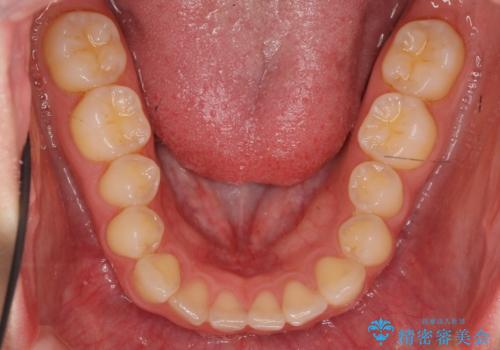

下の前歯が1本短い インビザラインと部分矯正の組み合わせ

- 前歯のガタつきと、下の前歯が一本短いことを主訴に来院。

インビザラインのマウスピースではめる装置で歯を引っ張り出すことは難しいと説明し、下の前歯だけワイヤー部分矯正を行ってからインビザライン矯正で仕上げをしました。

周りには気にしなくていいのではと言われていたが、やってよかったと非常に満足されていました。

難しい部分を短期間ワイヤー矯正を行ってからのインビザラインは、全体治療が短くなるだけでなく、仕上がりもよくなるのでオススメです。